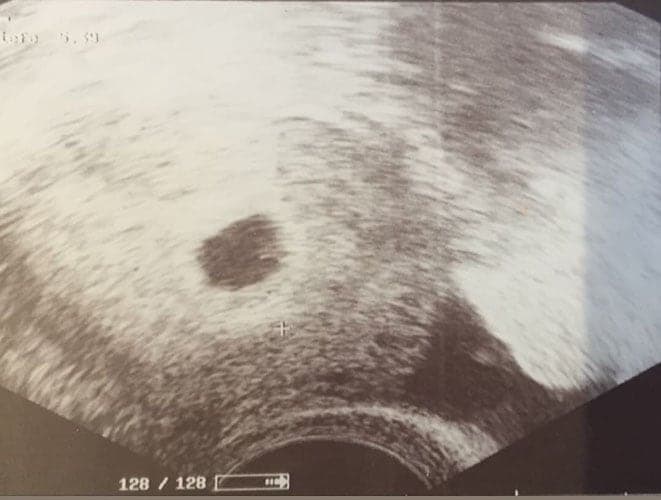

Ultraschallbilder aus dem 2. Trimester (13. bis 28. SSW)

Im 2. Trimester bekommt man oft die schönsten "Ganz-Körper" Ultraschallbilder. Das Baby ist nun so groß, dass man alles gut erkennen kann und noch nicht zu groß, so dass es noch ganz auf das Bild passt. In dieser Zeit lässt sich meist das Geschlecht bestimmen, wobei manche Babys es einfach nicht preis geben wollen und sich immer so drehen, dass man nichts erkennen kann.